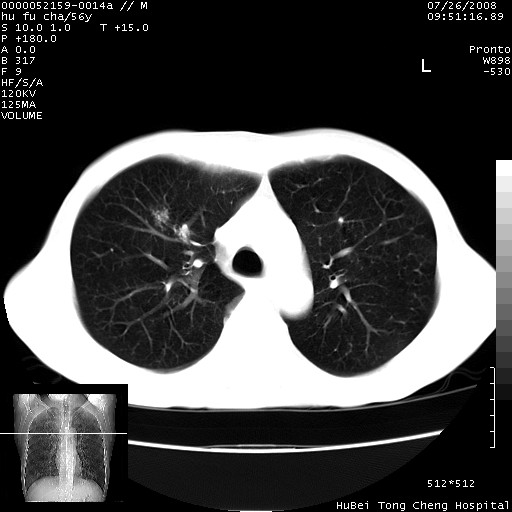

以下是引用zsl6918在2008-8-25 22:47:00的发言:[br]胸骨,胸椎及肋骨均可见多发转移表现,肝内低密度结节不除外转移。原发灶可能在右肺。双侧可见支扩表现。

以下是引用卜一在2008-8-26 8:02:00的发言:[br][br] 支持:肺癌并肺内,胸骨,胁骨,胸椎及肝内转移!另:左肺支气管扩张征伴感染! [br]

以下是引用zjzjr在2008-8-26 11:03:00的发言:[br]支持:肺癌并肺内,胸骨,胁骨,胸椎及肝内转移!另:左肺支气管扩张征伴感染!